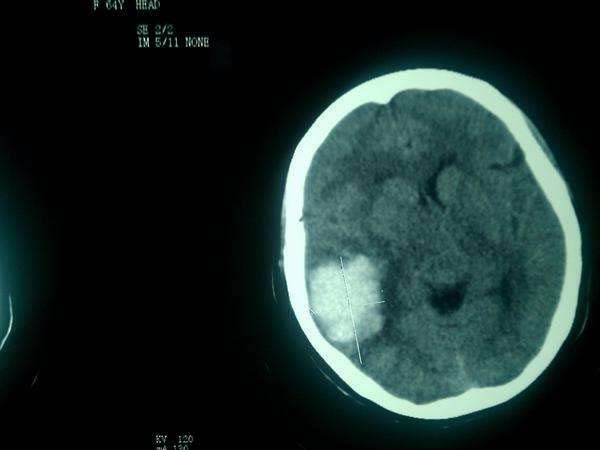

病例二

患者玄某某,女,90歲,濰坊市經(jīng)濟開發(fā)區(qū)邢石村人。2014年3月13日,患者突感眩暈,后重重摔倒在地,出現(xiàn)昏迷。家屬發(fā)現(xiàn)后立即撥打120求救,我院迅速派出救護車前往救治。

患者被接到醫(yī)院后,觀察出現(xiàn)呼吸不律且有呼吸短暫停止的跡象,瞳孔大小不等,情況十分危急。經(jīng)顱腦CT后診斷為“腦出血”。主管醫(yī)師當(dāng)即決定,為患者馬上進行腦出血微創(chuàng)手術(shù)。術(shù)后10天,患者意識清醒,身體指征正常,短暫休養(yǎng)后得以恢復(fù)出院。